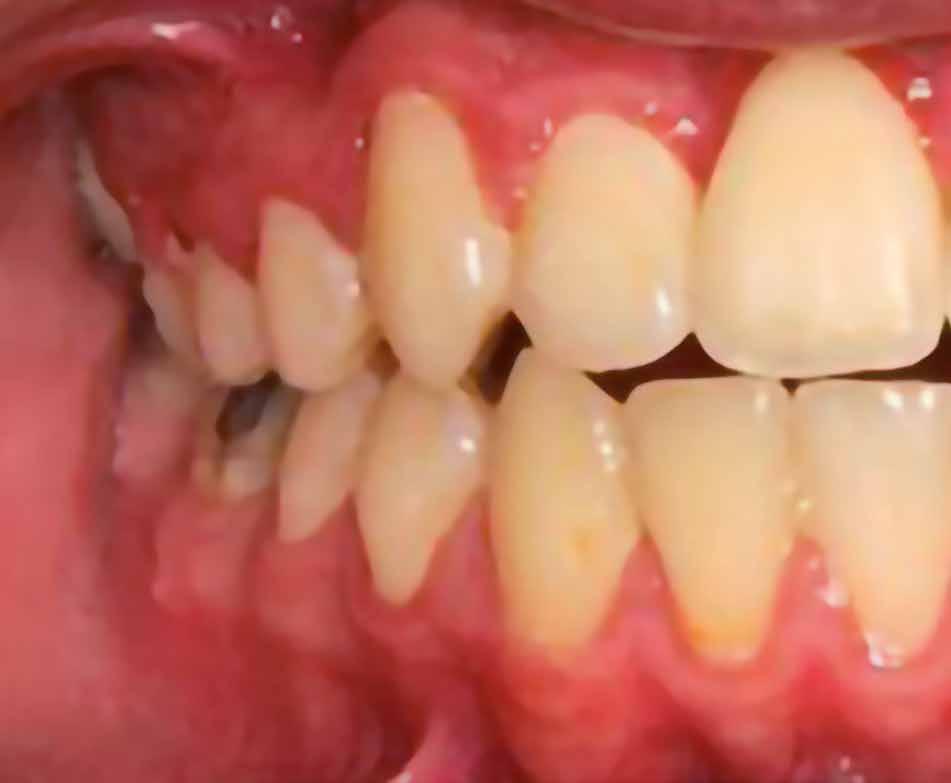

A parodontális elváltozások kezelésének elengedhetetlen része, hogy a páciens a kezelés teljes ideje alatt megfelelően együttműködjön a beavatkozásokat végző fogorvossal, és pontosan kövesse az utasításait. A megfelelő kooperáció elősegítése érdekében javasoljuk, hogy a kezelés minden fázisában egy intraorális szkenner (pl.: Condor; Biotech Dental) segítségével készült, 3 dimenziós modell segítségével ismertessük a páciensünkkel a szájüregi státuszának aktuális állapotát (2. ábra)

Az első találkozás alkalmával a kezelést igénylő terület állapotát egy intraorális szkenner segítségével rögzítjük. Ez a képalkotó eljárás kiegészíti azokat az általánosan alkalmazott vizsgálatokat, mint a radiológiai képalkotás (3. ábra) és a parodontális státuszfelvétel (4. ábra), továbbá hozzájárul a pontos diagnózis felállításához.

A szájüregi státuszról készült digitális 3 dimenziós modell bemutatása, továbbá a látottak részletes megbeszélése révén tudjuk a pácienseinket a leghatékonyabb módon motiválni. A páciensek kooperációját rendkívüli mértékben javítja, hogy ha a kezelési terv egyes lépéseinek megvalósítása után mindig bemutatjuk az aktuálisan elért eredményeinket, és ezáltal számára is jól láthatóvá és jól értelmezhetővé válik a kezelések célja.

2. ábra: A páciens számára a kezelés minden szakasza során bemutatásra kerülnek az intraorális szkenner segítségével készült felvételek. 3. ábra: Radiológiai felvételek. – 4. ábra: Parodontális szondával történő tasakmérés. 5. ábra: Egy háromdimenziós modell segítségével megfelelő információkkal látjuk el és motiváljuk a pácienst.